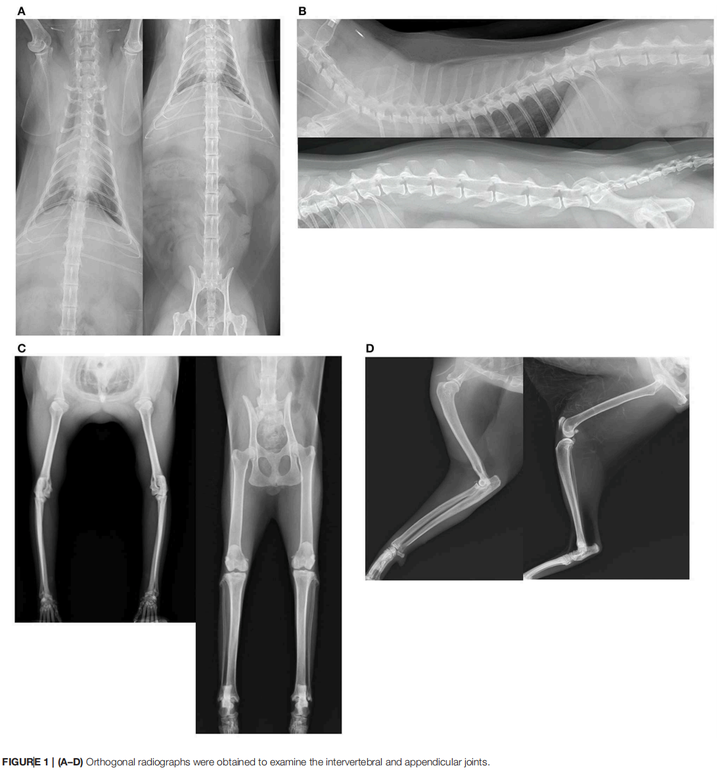

一只猫的关节已经在X光片上布满了退行性病变的痕迹,走路的时候每一步都在承受骨头磨骨头的摩擦,但它的主人什么都没察觉。

2020年,一个日本研究团队给101只猫做了全面的骨骼X光筛查,其中75只存在四肢关节退行性病变,41只存在脊椎退行性病变。

四肢关节有问题的75只猫里,主人注意到跛行的只有1位;脊椎有问题的41只里,主人注意到步态异常的也只有1位。整个研究中,兽医触诊时没有任何一只猫表现出明显的关节疼痛。